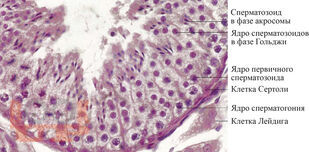

В учебном пособии рассматриваются вопросы, посвященные этиологии, патогенезу и современным методам диагностики варикоцеле, а также содержится информация о выборе тактики и способах лечения данной патологии. Учебное пособие предназначено для обучающихся по дисциплине «Урология», специальностям «Лечебное дело», «Педиатрия», а также для клинических ординаторов, обучающихся по специальности «Урология».